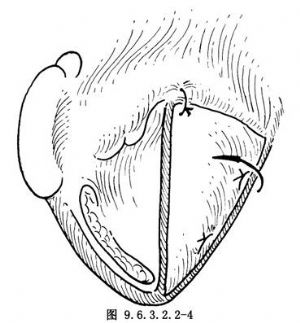

10.10 10.修復聲門裂

將預先形成的患側軟骨瓣(患側橫徑全長,寬0.5cm的軟骨條),翻入聲帶已切除側喉腔,用0號細絲線縫合固定,前方固定在環狀軟骨上,後方固定在後板上分離梨狀窩黏膜,遮蓋在軟骨瓣上間斷縫合(圖9.6.3.2.2-4)。此時改爲淺麻醉,用吸引管頭刺激喉氣管黏膜,觀察健側聲帶活動時是否達到聲門閉合。如聲門裂大,可取帶狀肌遊離肌瓣植入軟骨瓣上的梨狀窩黏膜下,再重新縫合梨狀窩黏膜(圖9.6.3.2.2-5)。

胸骨舌骨肌蒂修復法:預先將患側胸骨舌骨肌和舌骨一併遊離,形成舌骨胸骨舌骨肌蒂,將舌骨翻向患側喉腔,將靠舌骨的肌蒂前方縫合固定在環甲膜或環狀軟骨弓上,後方縫合固定在環狀軟骨後板上。此時舌骨已嵌於患側喉腔,達到縮小聲門裂目的。